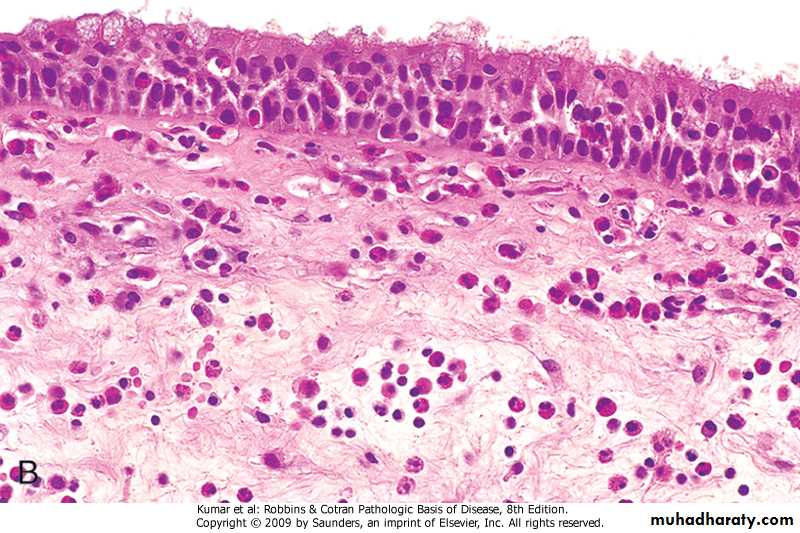

Bronchial Asthma : Pathology

Gross: The lung are overinflatedMicroscopical:

1.The lumen of the bronchi and bronchiole contain thick mucus plug (containing whorls of epithelium called curschmann spirals),charcot leyden crystals and eosinophils

2. The basement membrane shows characteristic hyaline thickening

3. The submucosa shows congestion . edema and infiltration by esinophil & mast cells

4. The bronchial muscle are hypertrophied

Bronchial mucosa in Asthma